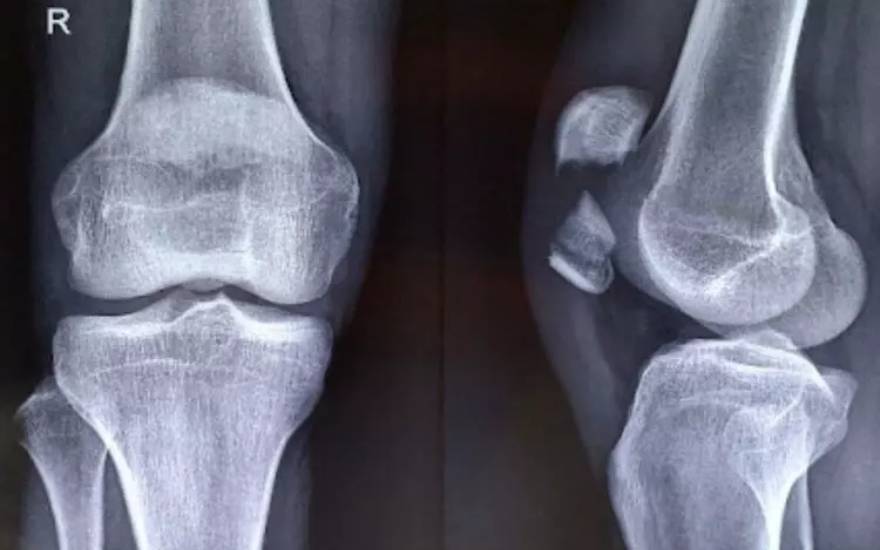

髌骨是保护膝关节前侧的重要结构,对支撑膝盖活动、实现腿部伸展弯曲及保持平衡具有关键作用。该病是指髌骨出现裂痕或碎裂成多块的重度损伤。髌骨一旦碎裂,膝关节活动能力将显著下降,引发疼痛并严重影响日常行动。

手术复位内固定

在髌骨严重粉碎、明显移位或出现游离骨块的情况下,手术治疗是更为有效的选择。医生会通过骨折复位内固定手术,将分离的骨折块重新对位并牢固固定,以恢复髌骨的正常结构和功能,从而降低日后发生关节错位或活动功能障碍等并发症的风险。

严重髌骨骨折通常需要通过手术进行骨折内固定治疗